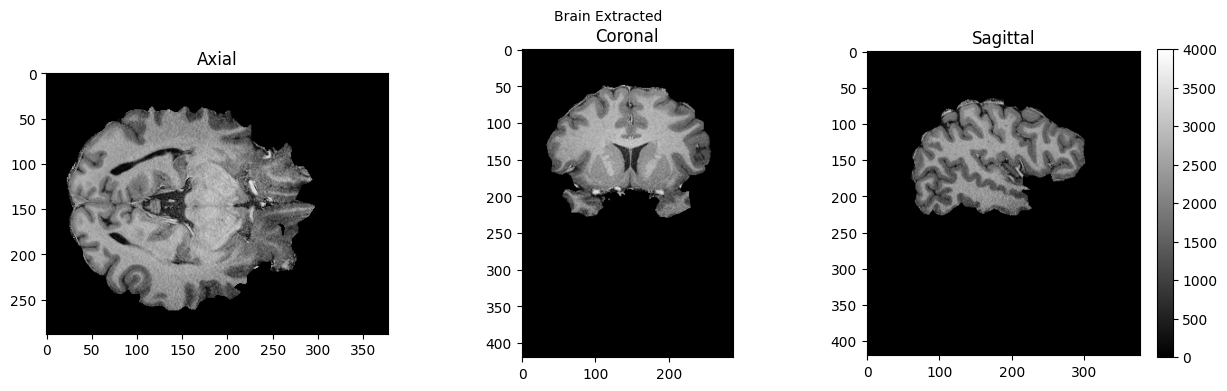

btr = fsl.BET()

btr.inputs.in_file = './sub-01_ses-01_7T_T1w_defaced.nii'

btr.inputs.frac = 0.4

btr.inputs.out_file = './sub-01_ses-01_7T_T1w_defaced_brain.nii'

res = btr.run()

brain = nib.load('./sub-01_ses-01_7T_T1w_defaced_brain.nii.gz').get_fdata()

view_slices_3d(brain, slice_nbr=230, vmin=0, vmax=4000, title='Brain Extracted')